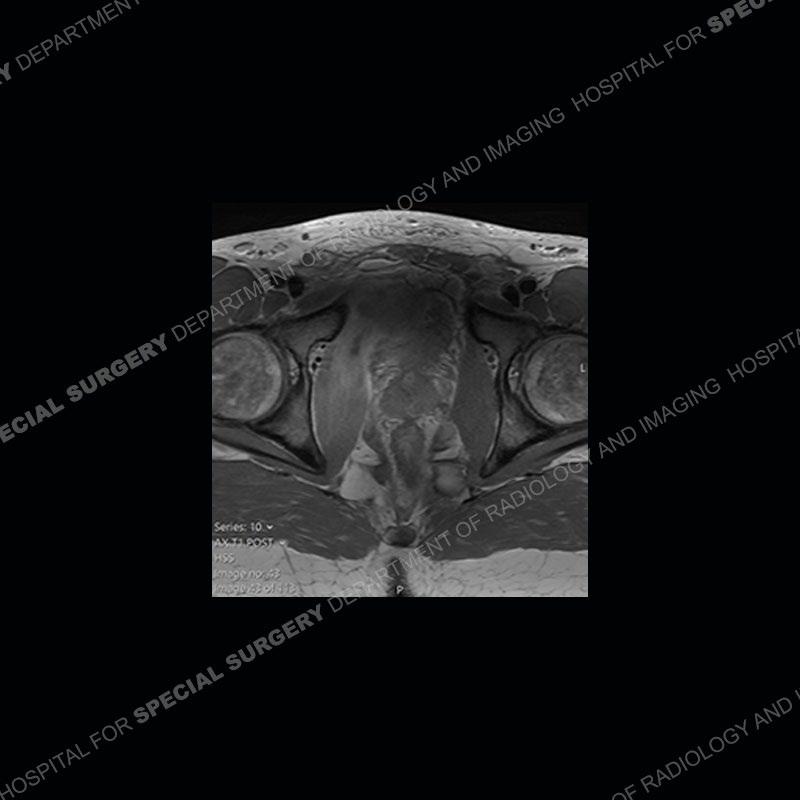

Radiographs did not demonstrate any clear abnormality. The MRI shows markedly abnormal signal of the right superior pubic ramus and abnormal signal/”mass” extending into the adjacent soft tissue. The inferior articular surface of the ramus showed what was thought to be bony destruction. CT examination shows a destructive process of the right superior pubic ramus.

Subsequent MRI in a very short time interval shows markedly increased abnormality of the ramus and increased edema and “mass” of the soft tissue. Post contrast imaging shows multiple, rim enhancing collections of the soft tissue and similar albeit less conspicuous enhancing collection of the ramus.

Diagnosis: Osteomyelitis and Soft Tissue Abscess